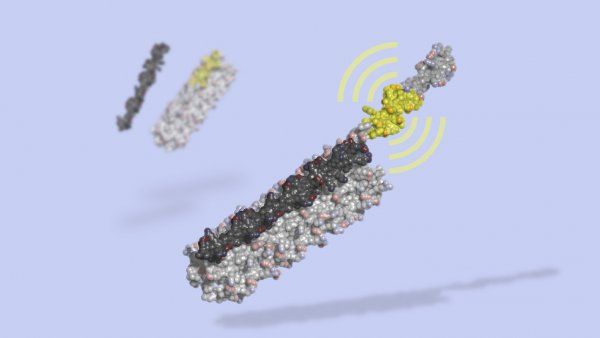

Scientists at UCSF, in collaboration with colleagues at UNC, have developed the world’s largest virtual pharmacology platform and shown it is capable of identifying extremely powerful new drugs.